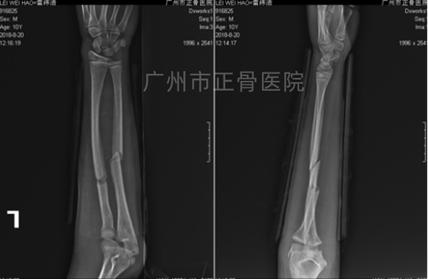

X线片检查示:左侧桡尺骨中上段骨折,骨折近端向掌侧移位及成角。

▲复位前,骨折端明显重叠移位